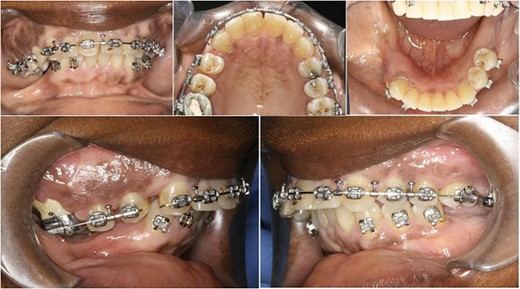

The operation planned was a Le Fort I osteotomy with a right posterior segment osteotomy, which would set back the upper incisors by 6 mm, impact the upper left second molar by 4 mm and impact the posterior segment from the upper right first premolar (by 5 mm) to the upper right first molar (by 12 mm). No forward movement of the maxilla was planned. The segmental osteotomy was performed following down fracture of the maxilla and the final occlusion was aligned to a full coverage occlusal splint. The right descending palatal artery was sacrificed.

The maxillary mucosa appeared pale during the procedure, but showed capillary refill. The patient presented with wound infection and avascularity of the maxilla 1 week after the procedure. She was treated with intravenous Co-amoxiclav for 2 weeks. A course of hyperbaric oxygen treatment was organized at 14 and 18 days post-operatively. She was started on therapeutic doses of Pentoxyfylline and Vitamin E to improve capillary blood flow.